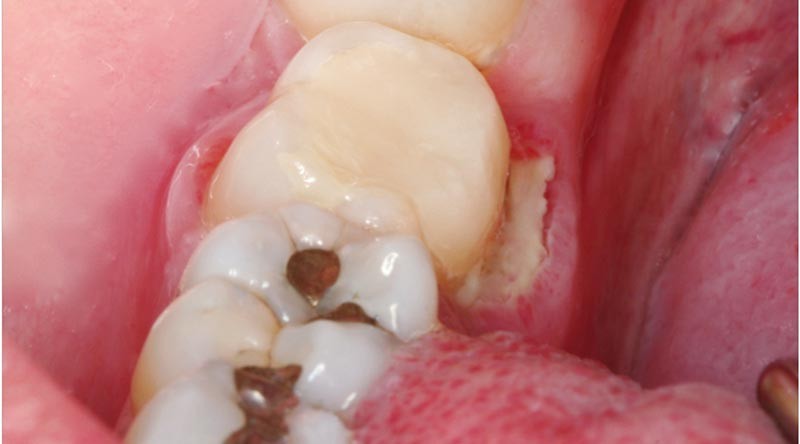

Sur la 47, on observait une volumineuse obturation provisoire reconstituant la face linguale et une exposition de l’os alvéolaire, au contact de la 47, sur toute la longueur de la face linguale et sur une largeur de 6 mm.